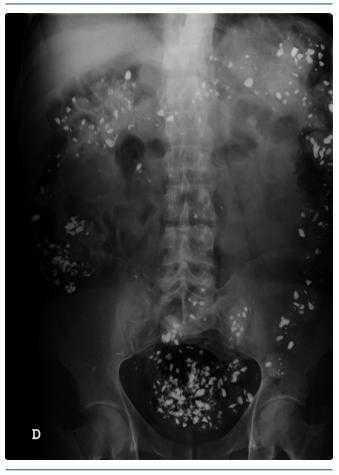

El control de la hiperfosfatemia en pacientes con insuficiencia renal crónica es un problema mayor 1. El carbonato de lantano es un nuevo fármaco (metal pesado) empleado para su control. Se administra por vía oral con buena tolerancia, es absorbido en el intestino y se acumula en el organismo 2. Presentamos la imagen radiológica de su acumulación intestinal mantenida a los 15 días después de haberse suspendido su administración (figura 1).

Figura 1.